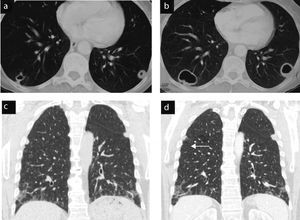

Clinical ObservationCase 1 (Fig. 1)This patient was a 72-year-old male, diagnosed with RA 5 years prior, a non-smoker, and rheumatoid factor (RF) positive. In the preoperative chest radiograph we detected lung nodules. Asymptomatic computed tomography of the chest shows multiple nodules, predominantly subpleural, some larger (3cm) and cavitated with irregular borders. During follow-up, a transthoracic biopsy, was performed and rheumatoid nodules werediagnosticated.1

Case 1. Typical and atypical nodules. (a) Preoperative chest radiograph with multiple pulmonary nodules. (b) CT scan of the chest: larger nodules in upper lobes, irregular surface and contour, neoplasia was ruled out by percutaneous biopsy and the diagnosis of rheumatoid nodules was reached. (c) CT scan of the chest: well demarcated, subpleural rounded nodules in lower lobes (parietal pleura, mediastinum, fissures (asterisk)), some isolated and cavitated (arrow). The radiographic appearance is typically of rheumatoid nodules.